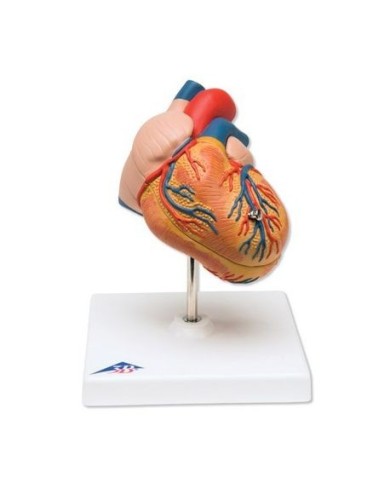

Fra i modelli di base segnaliamo il modello di cuore classico in due parti, in cui le due metà del cuore sono tenute insieme da potenti magneti.